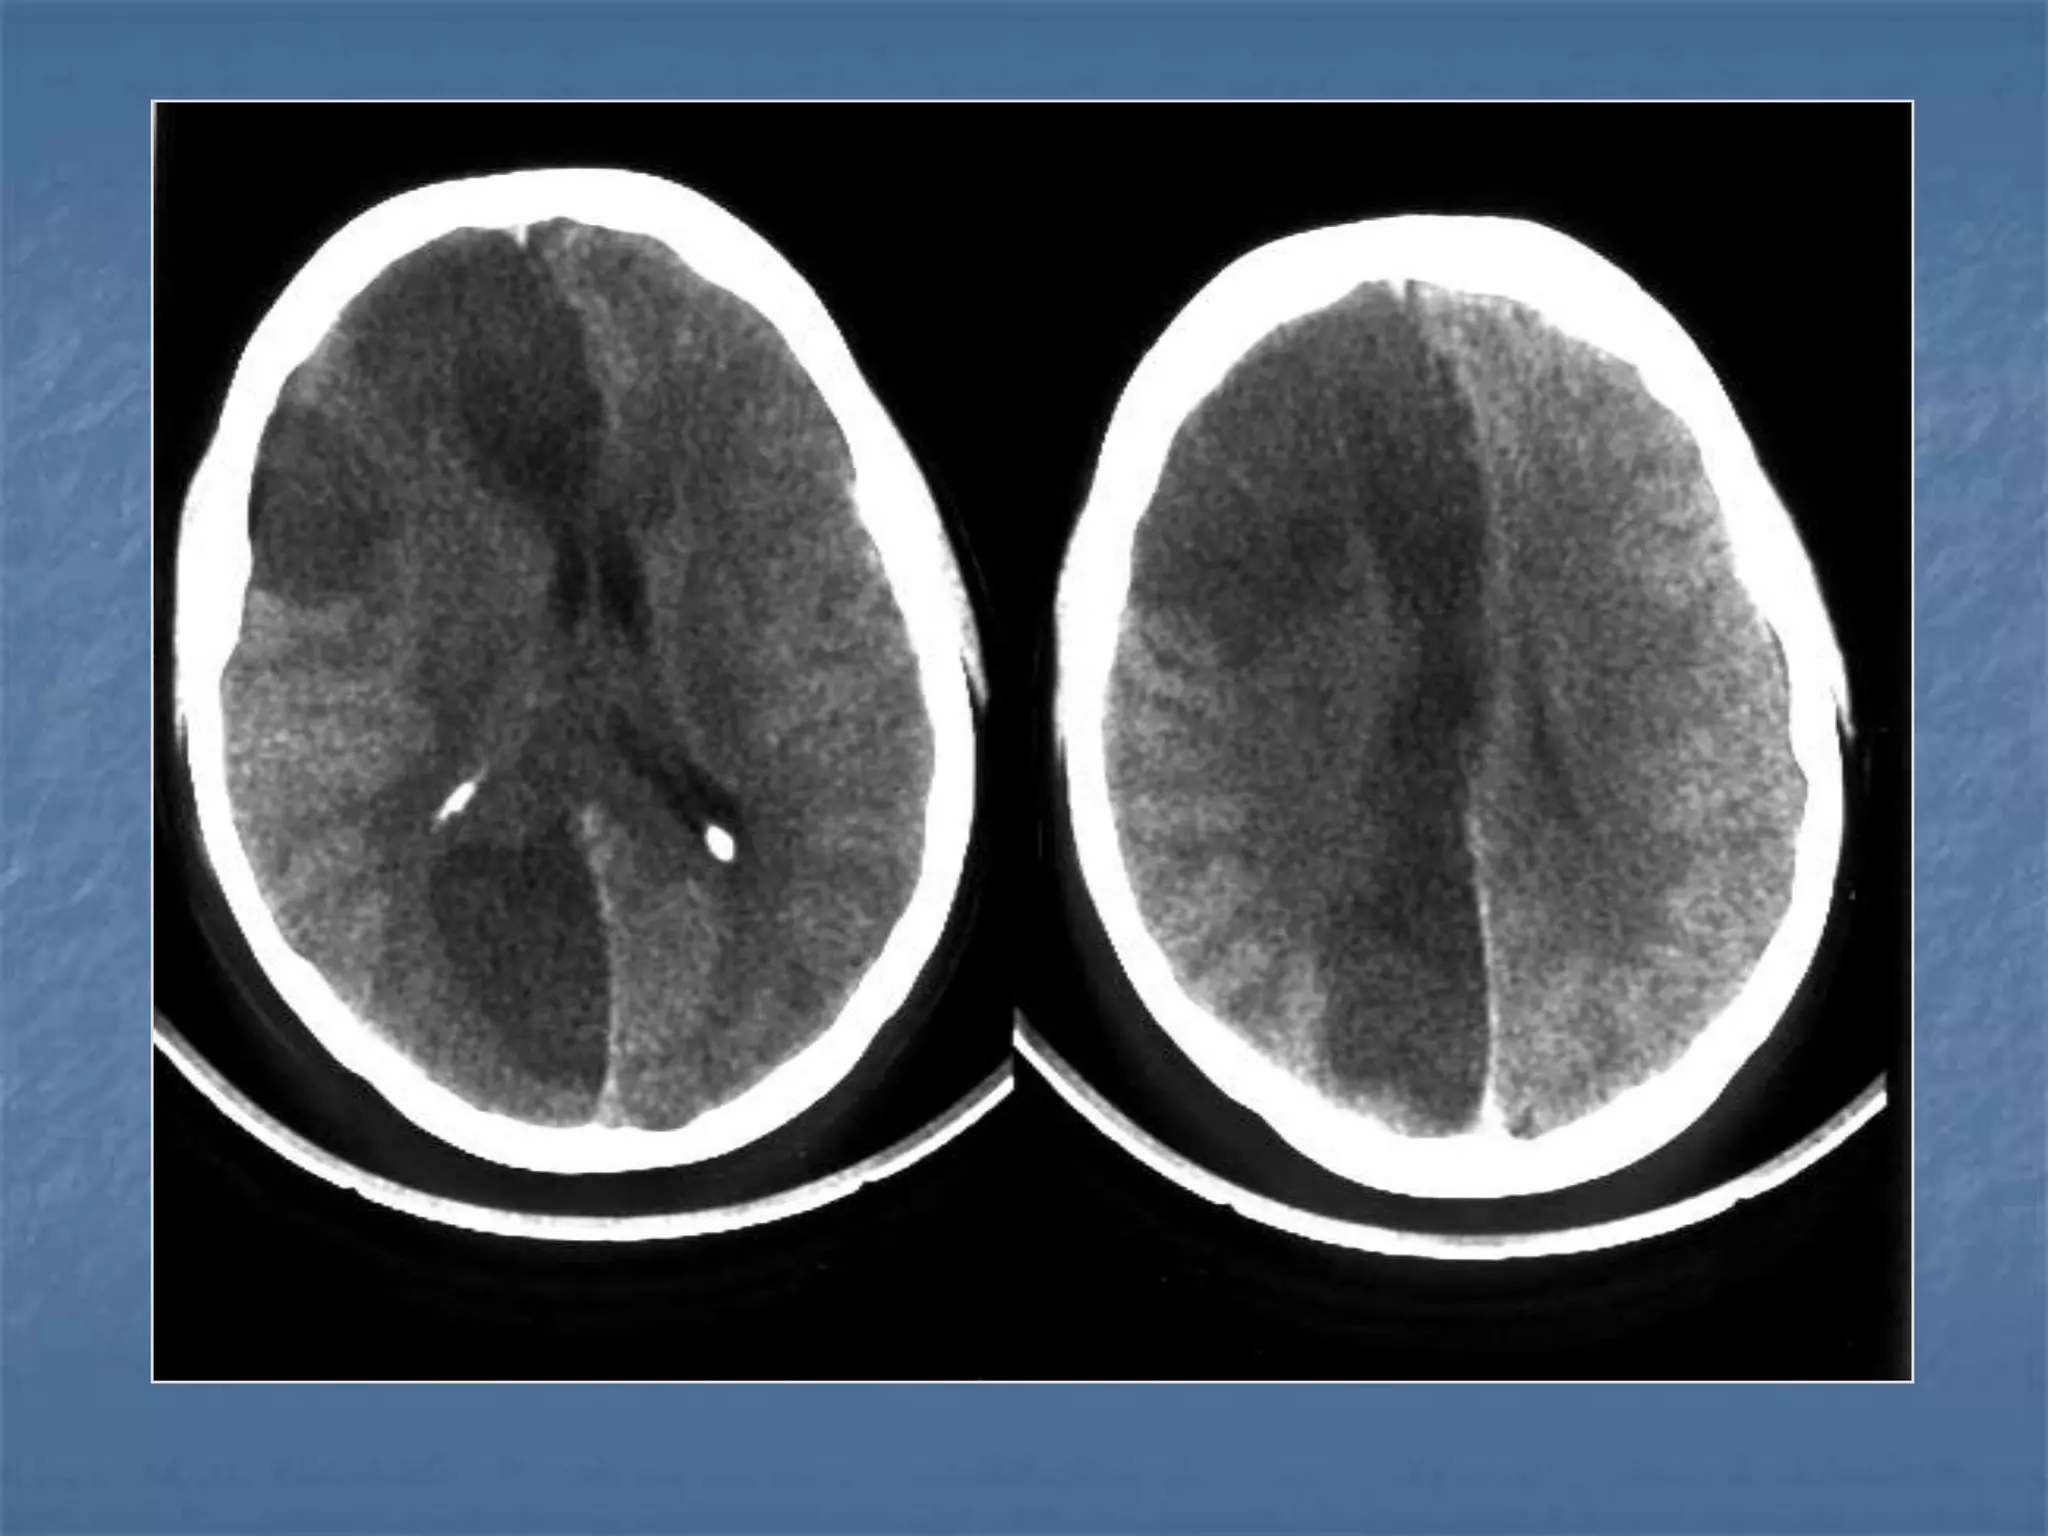

Diffuse Axonal Injury

 Diffuse axonal injury is often referred to as "shear injury". It is the most

common cause of significant morbidity in CNS trauma. Fifty percent of all

primary intra-axial injuries are diffuse axonal injuries. Acceleration,

deceleration and rotational forces cause portions of the brain with

different densities to move relative to each other resulting in the

deformation and tearing of axons. Immediate loss of consciousness is

typical of these injuries. The CT of a patient with diffuse axonal injury may

be normal despite the patient's presentation with a profound neurological

deficit. With CT, diffuse axonal injury may appear as ill-defined areas of

high density or hemorrhage in characteristic locations. The injury occurs in

a sequential pattern of locations based on the severity of the trauma. The

following list of diffuse axonal injury locations is ordered with the most

likely location listed first followed by successively less likely locations:

- Subcortical white matter

- Posterior limb internal capsule

- Corpus callosum

- Dorsolateral midbrain